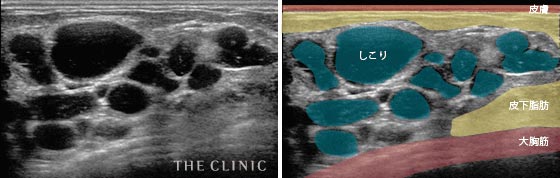

- しこりの数

- 複数のしこりができてしまった症例